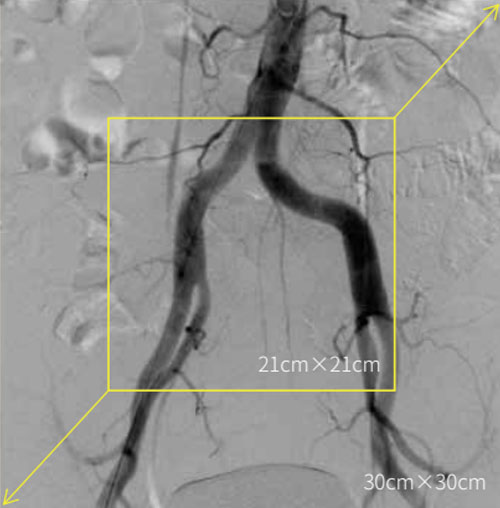

DSA is used to clearly visualize blood vessels in a

bony or dense soft tissue environment. Images are produced using contrast medium by subtracting a “pre-contrast image” or mask image from subsequent images, once the contrast medium has been introduced into a structure.